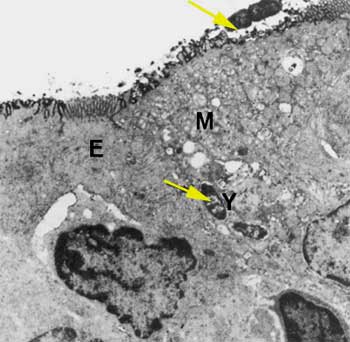

Yersinia (Y) dans une cellule M (M) contigue à un entérocyte (E)